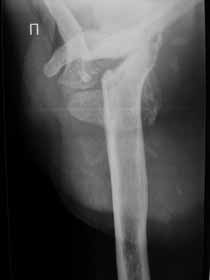

Не усмотрел в анамнезе "ноябре 2009 - травма с потерей сознания. В феврале 2010 г - первый рентген правого плечевого сутава - перелом анатомитеской шейки".

Все таки мы решили, что это посттравматичкский аваскулярный некроз. Принято волевое решение выполнить гемиартропластику. На операции: выраженная гипертрофия стенок субакромиальной бурсы. Она была раздута, на операции произведено ее вскрытие, эвакуировано 450 мл суставной геморрагической жидкости. По возможности бурса максимально иссечена, хотели промыть спиртовым расствором хлоргексидина, но побоялись. Вращ манжета - остатки ее найдены в задних отделах сустава, прикрепленные к большому бугорку. малого бугорка и сухожилия подлопаточной мышцы найдено на месте не было. нашли конечно, что-то похожее на сухожилие подлопаточной мышцы и пришили к кости, но я до конца не уверен. полость была дренирована. Сегодня 3 сут после операции - сустав отечен, из дренажа за сутки выделяется около 250 мл геморрагической жидкости. Однако это уже меньше чем в первые дни. Получает НПВС: нимулид по 1т 2 раза и диклофенак 1,0 в/м в сут. Вне зависимости от исхода, постараюсь рассказать об этом в следующих сообщениях. У кого есть мысли по этому, буду очень рад.